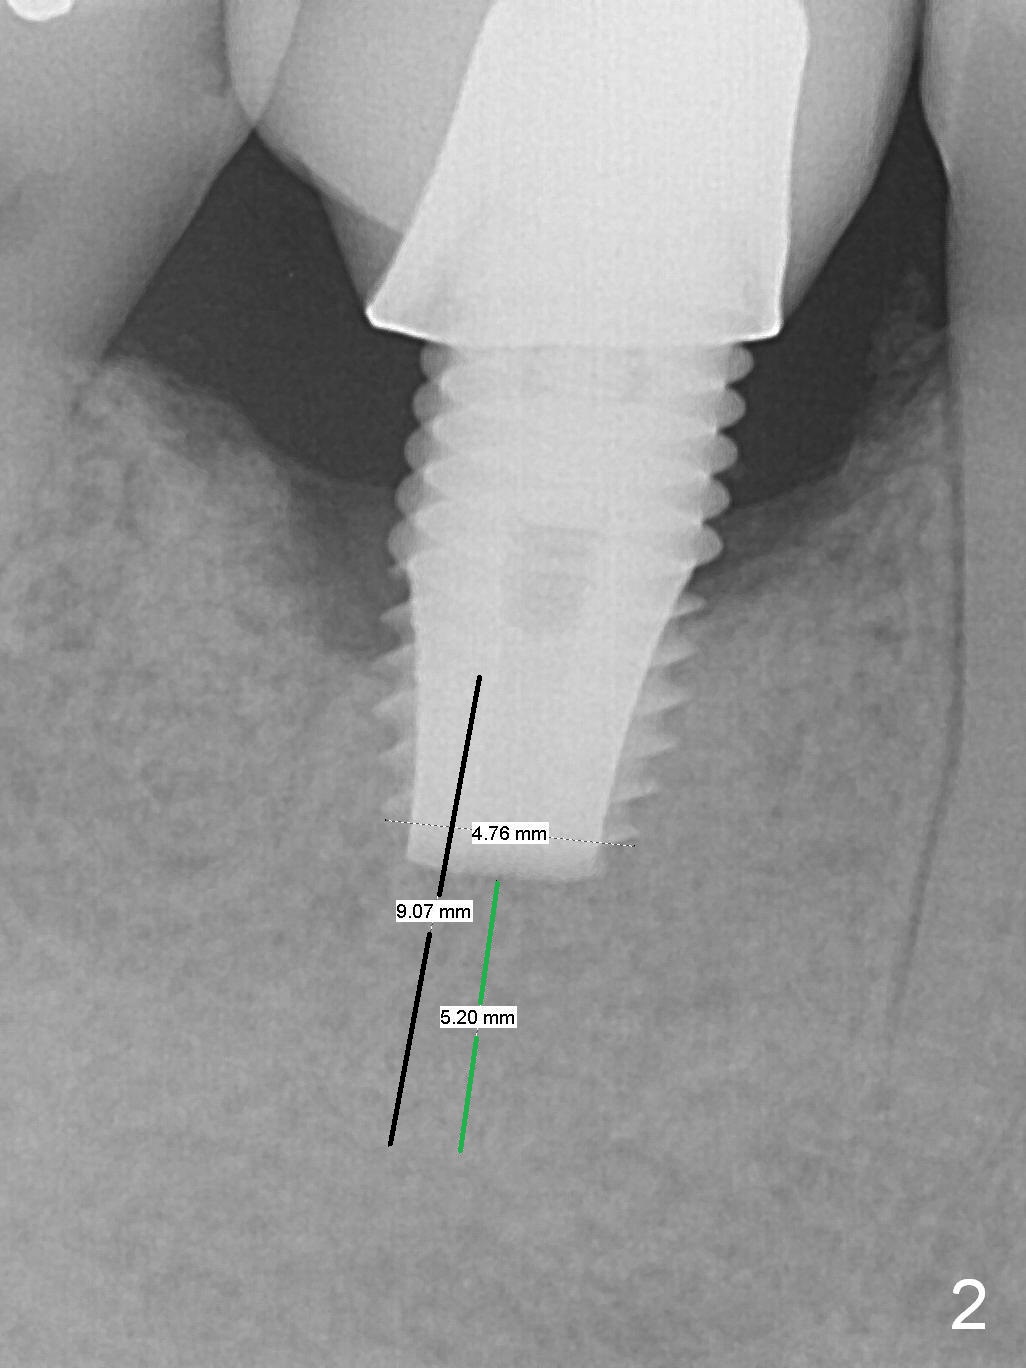

A 49-year-old man develops acute abscess of the lower right quadrant (Fig.3-5) secondary to periimplantitis at #30 (Fig.1,2,6). The latter is probably due to buccal placement (Fig.6 (*: buccal plate)). After removal of the infected implant, an osteotomy is established as lingual as possible using single drill modality (Fig.7 (4.3 mm Magic Drill after 1.6 mm pilot drill and Marking Bur, then Final Drill). With the single drill, the osteotomy does not shift buccally in spite of the lower buccal plate. A 5x9 mm IBS implant is placed lingually as planned (Fig.8 (>40 Ncm)), followed by an angled abutment (5 mm x 15° (4 mm)) (Fig.9 A). The buccal gap is filled with autogenous bone, allograft (.5-1.5 mm) and Osteogen (Fig.10 *), covered by resorbable and non-resorbable membranes. After suturing, periodontal dressing is applied.